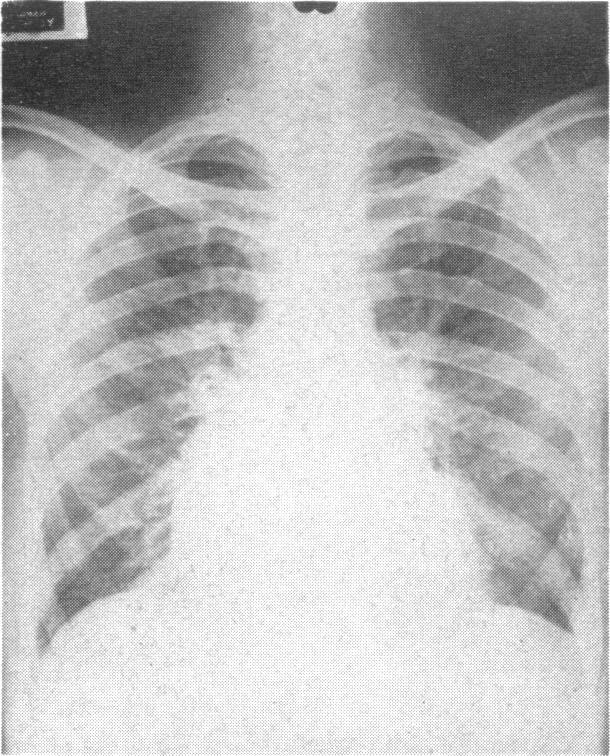

Association of cardiac pulmonary haemosiderosis and fibrosis.